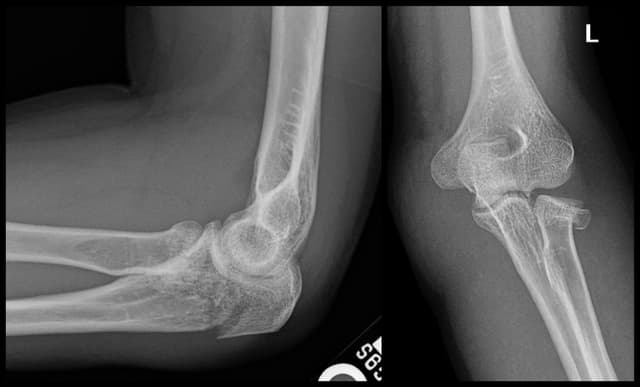

Imaging

Pre-op